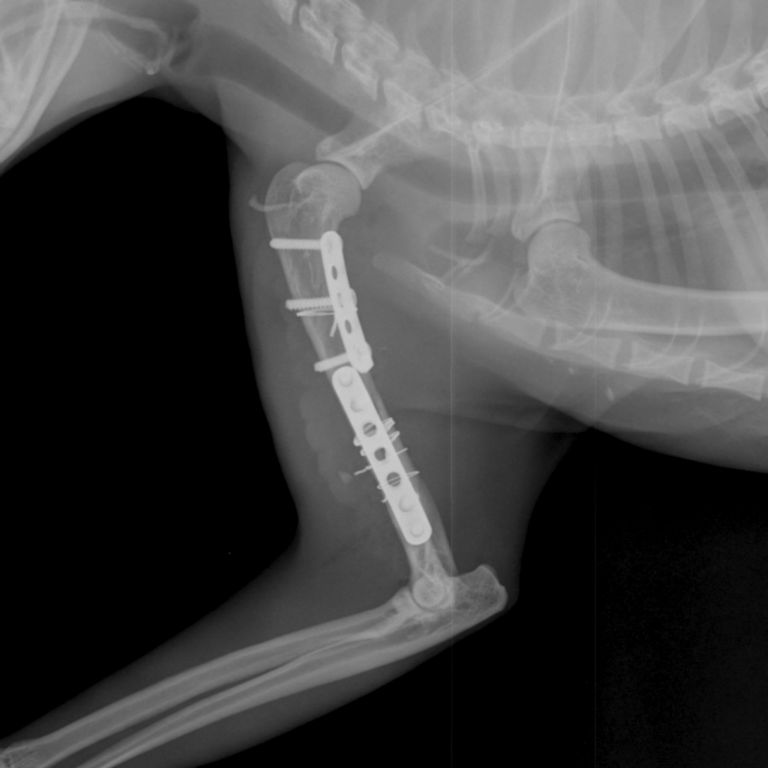

Рентгеновские снимки перелома лапы у кота: диагностика и лечение